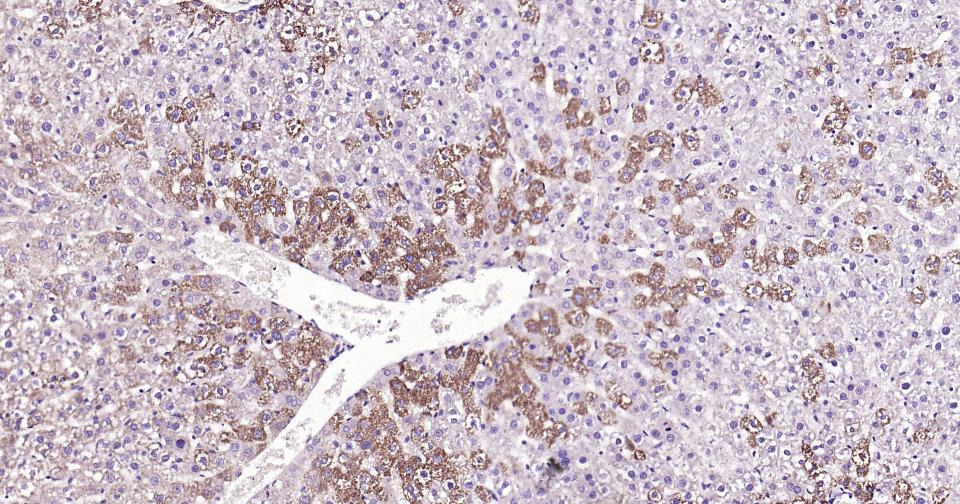

| IHC-P | Human, Mouse, Rat | 1:100-500 | |